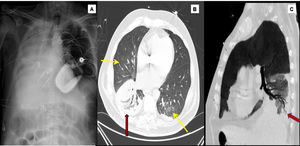

1A) Radiografía de tórax. Atelectasia subtotal del pulmón derecho, cánula de eyección de ECMO en yugular derecha y cánula de succión en vena cava inferior.

Tomografía computarizada con contraste (fase arterial, ventana de pulmón). 1B) Se observan focos de infiltrado en vidrio deslustrado (flechas amarillas) pulmonares bilaterales de predominio central. Consolidación en lóbulo inferior derecho (flecha roja). 1C) Se demuestra la permeabilidad del árbol bronquial en el seno del foco consolidativo.

Se mantuvo soporte con ECMO con flujo de 4l/min y FiO2 para PaO2>60mmHg, bajo ventilación protectora, sin anticoagulación y broncoscopias diarias hasta conseguir extraer el material trombótico en su totalidad. Tras 4 días en ECMO se consiguió reexpansión del pulmón derecho sin nuevos sangrados bronquiales. A continuación, se procedió a prueba de desconexión de ECMO-venovenosa y posterior decanulación. Tras ello se realizó estudio con una tomografía computarizada con contraste en fases arterial y venosa que detectó una imagen de condensación basal derecha sin objetivarse puntos sangrantes en la circulación bronquial, fístulas, cavitaciones u otras lesiones (fig. 2). Se atribuyó finalmente la hemoptisis a sangrado en relación con neumonía en presencia de hipertensión pulmonar y anticoagulación. En las siguientes semanas evolucionó de forma paulatina recibiendo alta el día 69 de ingreso.